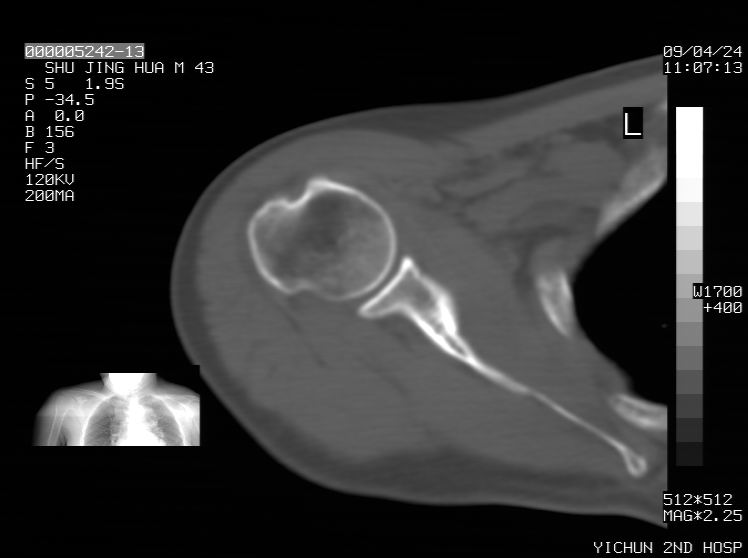

标题: CT19569:请会诊,女50岁,右肩疼痛数月 [打印本页]

标题: CT19569:请会诊,女50岁,右肩疼痛数月

钙化性肌腱炎

是指钙盐沉积在变性肌腱中的一种无菌性炎症,常见于肩关节的肩袖肌腱,引起肩部疼痛和活动受限。分为急性和慢性两种类型,急性型有肩关节突然出现急性疼痛的发作史,夜间可痛醒。

以下是引用余辉在2009-4-24 15:24:00的发言:[br]考虑钙化性肩周炎,肱二头肌长腱或相应附属组织钙化